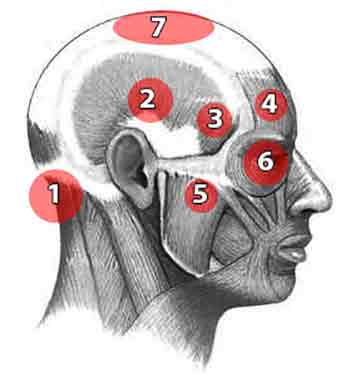

I have suffered from headaches many times during my long life. This means that I have had the

opportunity to observe the physical and physiological factors which create them.

I have suffered from headaches many times during my long life. This means that I have had the

opportunity to observe the physical and physiological factors which create them.All too often a headache is on one side only as the image shows. They are due to a number of factors most often overlooked by those who are ignorant of the tension patterns which cause them. You do not have to put up with pills, poor diagnosis and inadequate treatments.

There are several common causes of headaches. Here are some of the most prevalent:

Tension headaches: These are by far the most common type of headache and typically result from muscle tension and vertebral displacement. They often cause a mild-to-severe pain that feels like a toothache one side of the head. Migraines: Migraine headaches are more severe and can be accompanied by other symptoms such as nausea, sensitivity to light and sound, and visual disturbances. Sinus headaches: Inflammation or infection of the sinuses can cause pain in the forehead, cheeks, and around the eyes. Sinus headaches are often accompanied by nasal congestion and discharge. Medication overuse headaches: Frequent or excessive use of pain-relieving medications, such as over-the-counter analgesics or prescription drugs, can lead to medication overuse headaches. These headaches often occur when the effects of the medication wear off. Dehydration: Lack of proper hydration can cause headaches. It is important to drink enough water throughout the day to maintain hydration levels. Eye strain: Prolonged or intense use of digital devices, reading, or working in poor lighting conditions can strain the eyes and lead to headaches. Jaw tension: These are normally felt in the temple and over the eyes. Lack of sleep: Insufficient or poor-quality sleep can contribute to headaches. Establishing a regular sleep schedule and practicing good sleep hygiene can help alleviate this cause. Hormonal changes: Fluctuations in hormone levels, such as those experienced during menstruation, pregnancy, or menopause, can trigger headaches in some individuals. Certain foods and drinks: Certain foods and beverages, such as aged cheese, chocolate, caffeine, alcohol, and artificial sweeteners, have been known to trigger headaches in susceptible individuals.